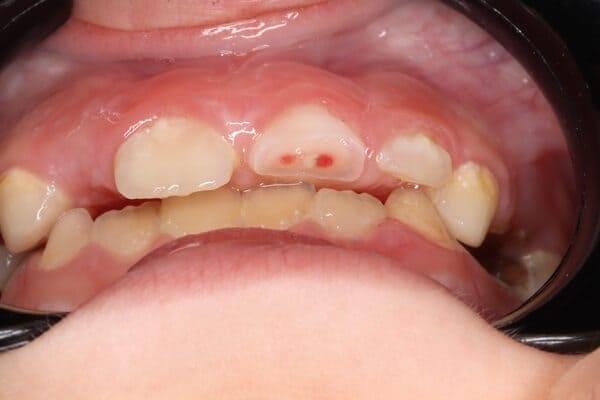

Навіть якщо візуально все в порядку...

​Бувають приховані травми: забій зуба, тріщина кореня або розрив судинного пучка. Якщо удару було завдано, але зуб на місці, все одно необхідно показатись дитячому стоматологу найближчим часом для проведення діагностики (рентген/фотопротокол) та складання прогнозу.